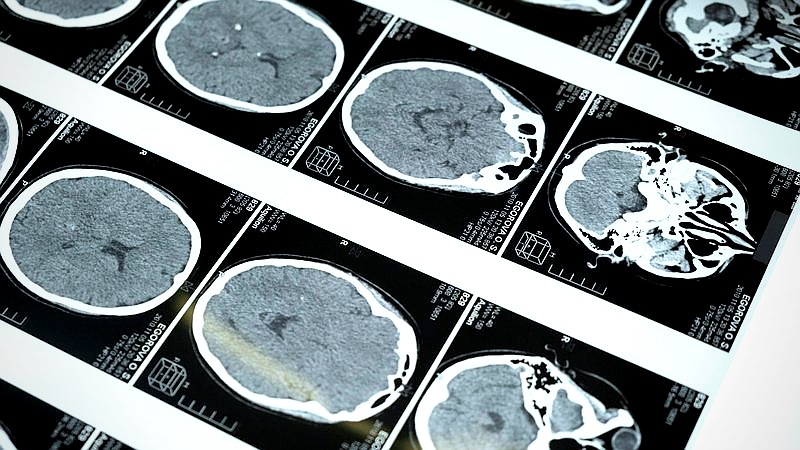

After what felt like an eternity of tests, scans, and hushed conversations, the doctor finally sat us down. Glioblastoma. Glioblastoma multiforme (GBM). The most aggressive type of brain tumor. The words hung in the air, heavy and suffocating.

GBM, as I quickly learned, is a grade IV tumor, meaning it grows rapidly and aggressively. The prognosis isn’t good. I won’t sugarcoat it. The average survival time after diagnosis is, frankly, terrifying. We were told about standard treatments: surgery, radiation, chemotherapy. But I felt like we needed more. I felt helpless, but I knew I couldn’t stay that way. I had to fight. Just something to think about. Check out our guide on HIV Exposure Accusations: SC Teacher’s Sex Crime Case. We covered this in Nutrient Deficiencies in Diabetes: Are You Getting Enough?.

AI proved invaluable in several key areas. First, it helped us identify potential clinical trials that Sarah might be eligible for. These trials often offer access to treatments that aren’t yet widely available. Finding them manually would have been like searching for a needle in a haystack. The AI algorithms could sift through trial criteria and match them to Sarah’s specific genetic profile and tumor characteristics.

Second, AI helped us analyze research papers and treatment protocols more efficiently. I could input specific search terms related to GBM, and the AI would generate summaries of relevant studies, highlighting key findings and potential implications for Sarah’s care. This allowed me to quickly grasp complex scientific concepts and stay up-to-date on the latest research.

AI can be helpful in analyzing medical images, but it’s not a replacement for a trained radiologist or oncologist. Accuracy varies depending on the algorithm and data used. For reliable health information, check out the National Institutes of Health: https://www.nih.gov/.